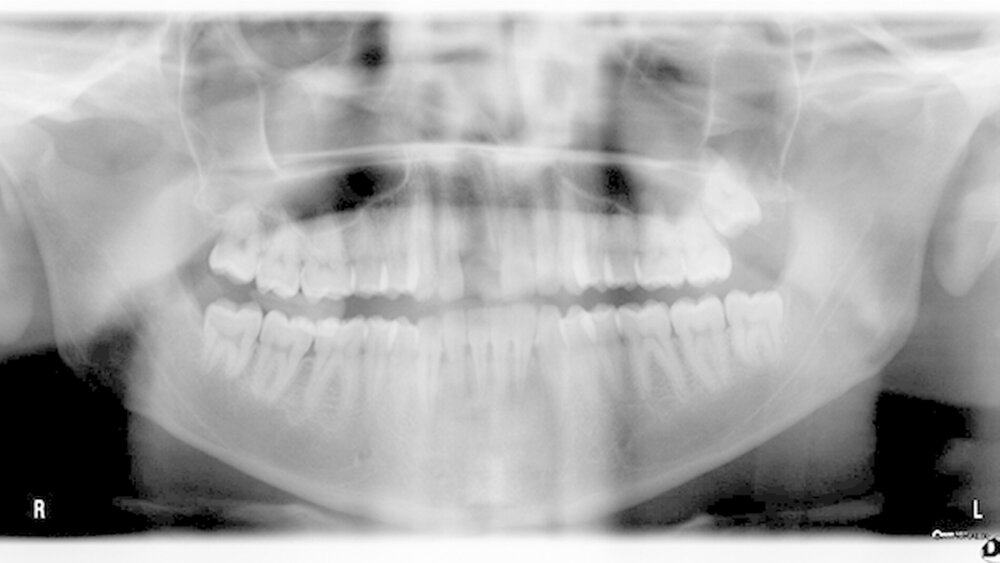

Der Zahn wurde zwei Stunden nach dem Unfall vital replantiert und semipermanent geschient. Die anschließende Abdrucknahme erfolgte unter allergrößter Sorgfalt. Die laborgefertigte Tiefziehschiene schließt die Bereiche der semipermanenten Schiene bis zum Schienenäquator mit ein. Was die Reanastomosierung der Gefäße und Nerven betrifft, ist der Behandler zuversichtlich, reagieren doch auch vital transplantierte Weisheitszähne nach einigen Wochen wieder auf Kältereize.